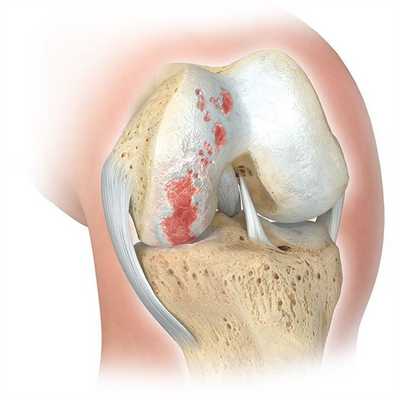

Главным показанием к оперативному вмешательству является гонартроз. Это дегенеративное заболевание коленного сустава, проявляющееся постепенным разрушением хрящевой ткани и деформацией нижней конечности. На поздних стадиях гонартроза у пациентов формируются вальгусные и варусные деформации. Объем движений ограничивается, возникает хронический болевой синдром.

Вмешательство рекомендуется проводить при удовлетворительном состоянии хрящевой поверхности костей и изолированном поражении одного участка коленного сустава. Такой метод коррекции дает возможность сохранить подвижность нижней конечности у молодых пациентов.

При неправильной оценке показаний остеотомия может ускорить дегенерацию коленного сустава. Перед лечением врачи проводят лабораторные исследования, получают снимки нижней конечности на протяжении и назначают дополнительные диагностические манипуляции.